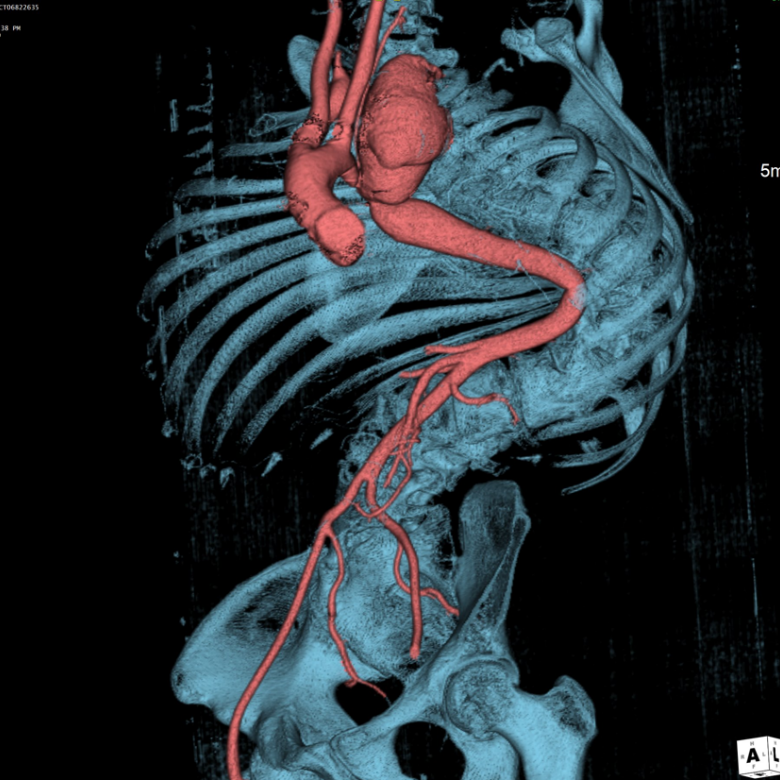

入院后完善进一步检查后发现患者主动脉病变复杂程度远远超过预期。术前检查显示患者左锁骨下动脉瘤最大直径达73.3mm,伴局限性夹层形成,目前瘤体已压迫喉返神经出现声音嘶哑症状,远期发生破裂猝死风险极高。同时,左锁骨下动脉开口近端合并主动脉缩窄,最狭窄处直径仅约10mm。更加雪上加霜的是该患者左椎动脉刚好单独起自主动脉弓狭窄处,且为左椎优势(图1)。结合患者脊柱侧弯畸形病史,进一步查体发现患者存在外耳道、四肢关节等多处畸形,完善基因检测后考虑诊断为Larsen综合征。鉴于患者病史、解剖和主动脉病变的复杂性,开放手术无法充分显露左锁骨下动脉瘤体,更加无法切除瘤体并重建左锁骨下动脉,且开放手术创伤和风险极大。而由于患者主动脉走行扭曲,介入手术存在支架无法输送至目标位置而失败的风险,且腔内重建椎动脉困难,一旦发生内漏,所有努力都将付诸东流。

术后患者安返重症监护室,术后6h患者苏醒并顺利拔出气管插管,第二天转回普通病房。患者术后恢复顺利,复查夹层动脉瘤CTA示主动脉支架位置准确,形态良好,弓上各分支血管血流通畅,左锁骨下动脉瘤隔绝良好,无内漏发生,术后第4天顺利出院。

术后复查3D图